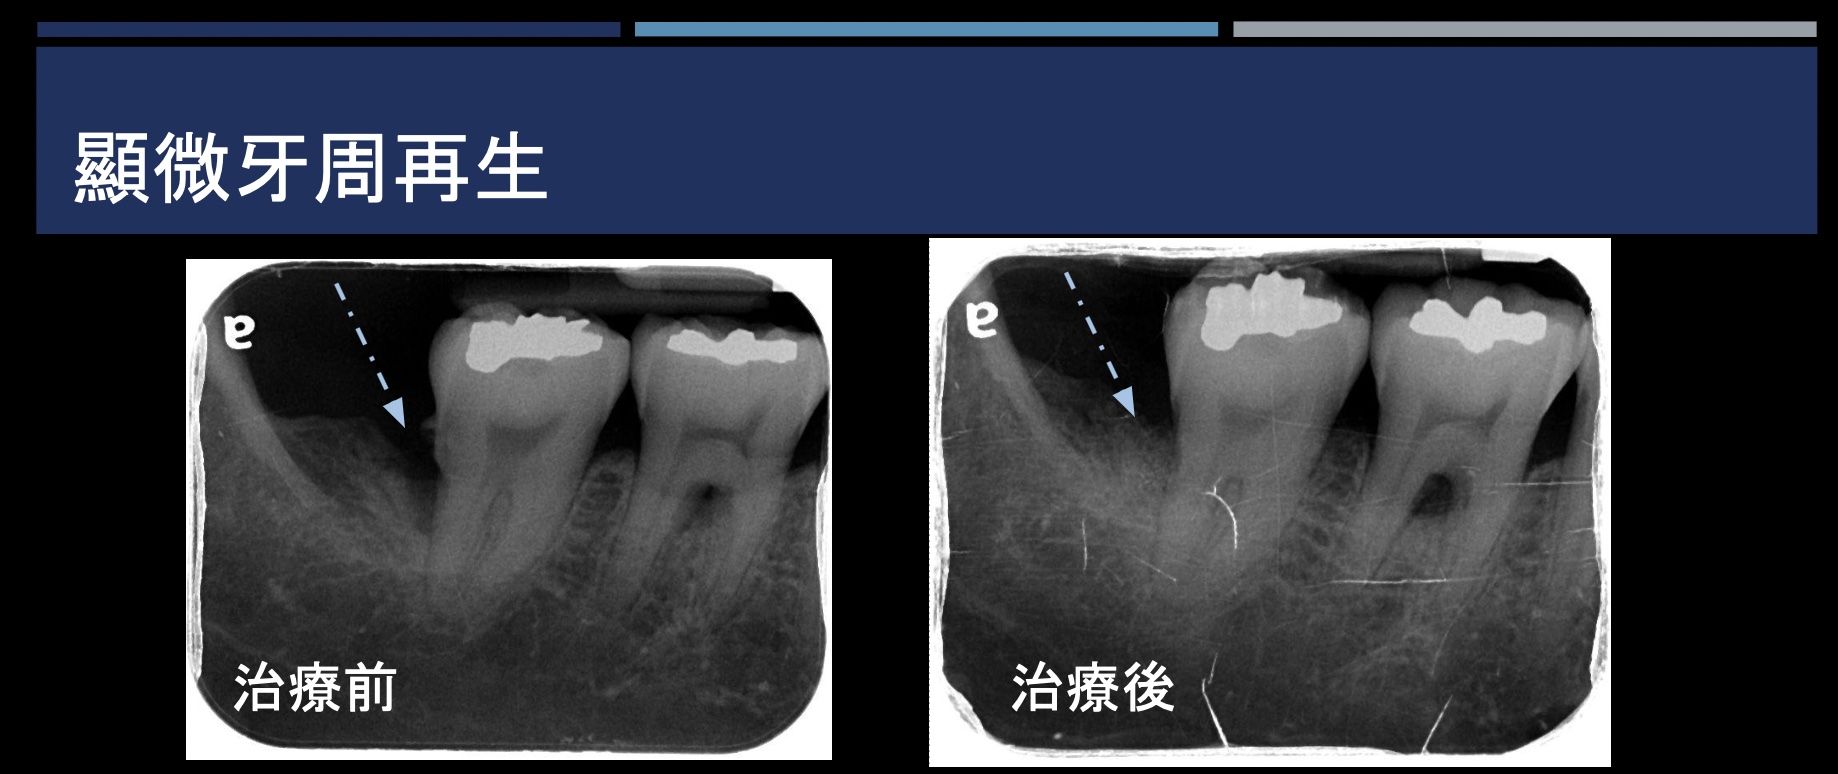

顯微牙周再生

牙齒周邊因為破壞所喪失的骨頭,在特定條件下可以進行重建再生,除了清除發炎,加上放置牙周再生材料(骨粉及再生膜),重建喪失的牙周,搭配顯微微創的方式,使手術傷口變小,術後恢復也較良好